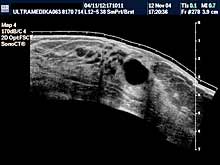

Vrsta i sadržaj pregleda Pregled

podrazumeva pregled tkiva (parenhima) dojki sa procenom limfnih žlezda

i krvnih sudova. Standardni pregled se radi primenom savremenih sondi

veće rezolucije i kompjuterizovanom ultrazvučnom tomografijom (Sono CT

i X -Res), kojom se mogu otkriti promene ispod 5 milimetara.

Primenjena tehnika:

- 2D broad band

- Sono C

- XRes

- 3D Sono CT

- Broad band-CD i CPD

- 3DCPA